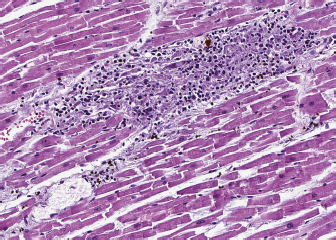

Fig. 2. Heart, dog. Myocardial interstitium is infiltrated by lymphocytes, with myofiber degeneration and necrosis. Hematoxylin and eosin.

A necropsy was performed. The main macroscopic finding consisted of a diffused megaesophagus. Low numbers of white, small-sized spots were also visible on the myocardial surface, with random distribution. The subsequent histology of the heart showed that myocardium was infiltrated by a severe multifocal to coalescing inflammatory process, mainly composed of lymphocytes, admixed with a lower number of macrophages, plasma cells and neutrophils, and rare giant multinucleated cells, with up to five haphazardly arranged nuclei. Inflammatory infiltrate was associated with small foci of necrotic cardiomyocytes with hypereosinophilic cytoplasm, loss of cross striations and pyknotic nuclei (Fig. 2). A similar inflammatory process consisting of multiple, variably sized foci of necrotizing myositis also involved esophageal and diaphragmatic skeletal muscle. Immunohistochemistry (IHC) was performed to characterize the inflammation involving the myocardium, esophagus and diaphragmatic skeletal muscle: the inflammatory cell population infiltrating the myocardium was mainly composed of CD3+ lymphocytes (T cells), admixed with a lower number of Iba1 positive macrophages, most of them being MHC-II positive. Rare, scattered B lymphocytes expressed CD20. Interestingly, a low proportion of cardiomyocytes expressed MHC-II in the cytoplasm or on the sarcolemma. Esophageal and diaphragmatic skeletal muscles were also characterized by an infiltration of T lymphocytes and macrophages. The histopathological picture was consistent with lymphocytic and necrotizing myocarditis and polymyositis.